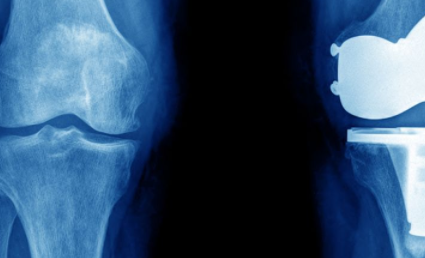

现在讲一下半月板切除,什么情况下需要进行半月板切除。我们在医学上将半月板的损伤分为三度。

一度损伤和二度损伤,建议保守治疗,不需要进行手术治疗。当半月板损伤达到三度,一般需要通过关节镜手术治疗,那么手术的具体方式有,半月板的全切除,半月板的全切,或者进行半月板的缝合术。

每一种方式都有它的适应症,在手术中我们在关节镜下,见到半月板损伤的具体情况,损伤发生的部位,撕裂的类型以及损伤的时间长短,来决定他的最终治疗方案。一般情况下靠近半月板游离缘,血供比较差,损伤以后无法愈合,要进行半月板的全切除。或者是半月板损伤时间非常长,撕裂的半月板组织蜕变明显,无法愈合,这种情况需要行半月板的切除。

如果损伤时间短,而且损伤区域靠近踝屈,也就是靠近关节囊侧,一般可以行半月板的缝合,所以具体要看哪种情况,有些情况是必须要进行半月板切除的。